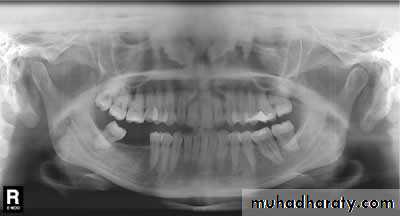

Bony abnormality, could be seen in rheumatoid arthritis or osteoarthrosis

1. OPG & Transcranial oblique lateral view.

Radiology

Dr. Mohammed Amjed Alsaegh, 2021

14